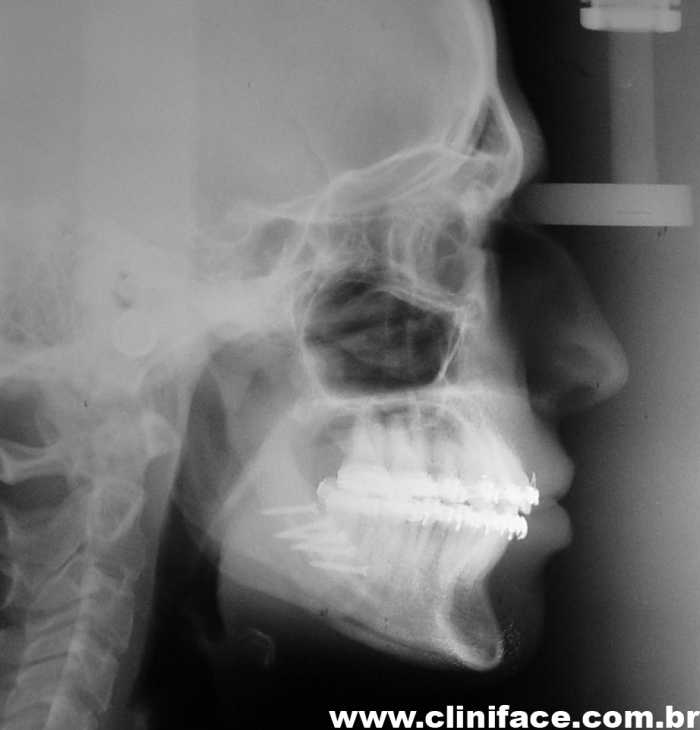

Telerradiografia inicial